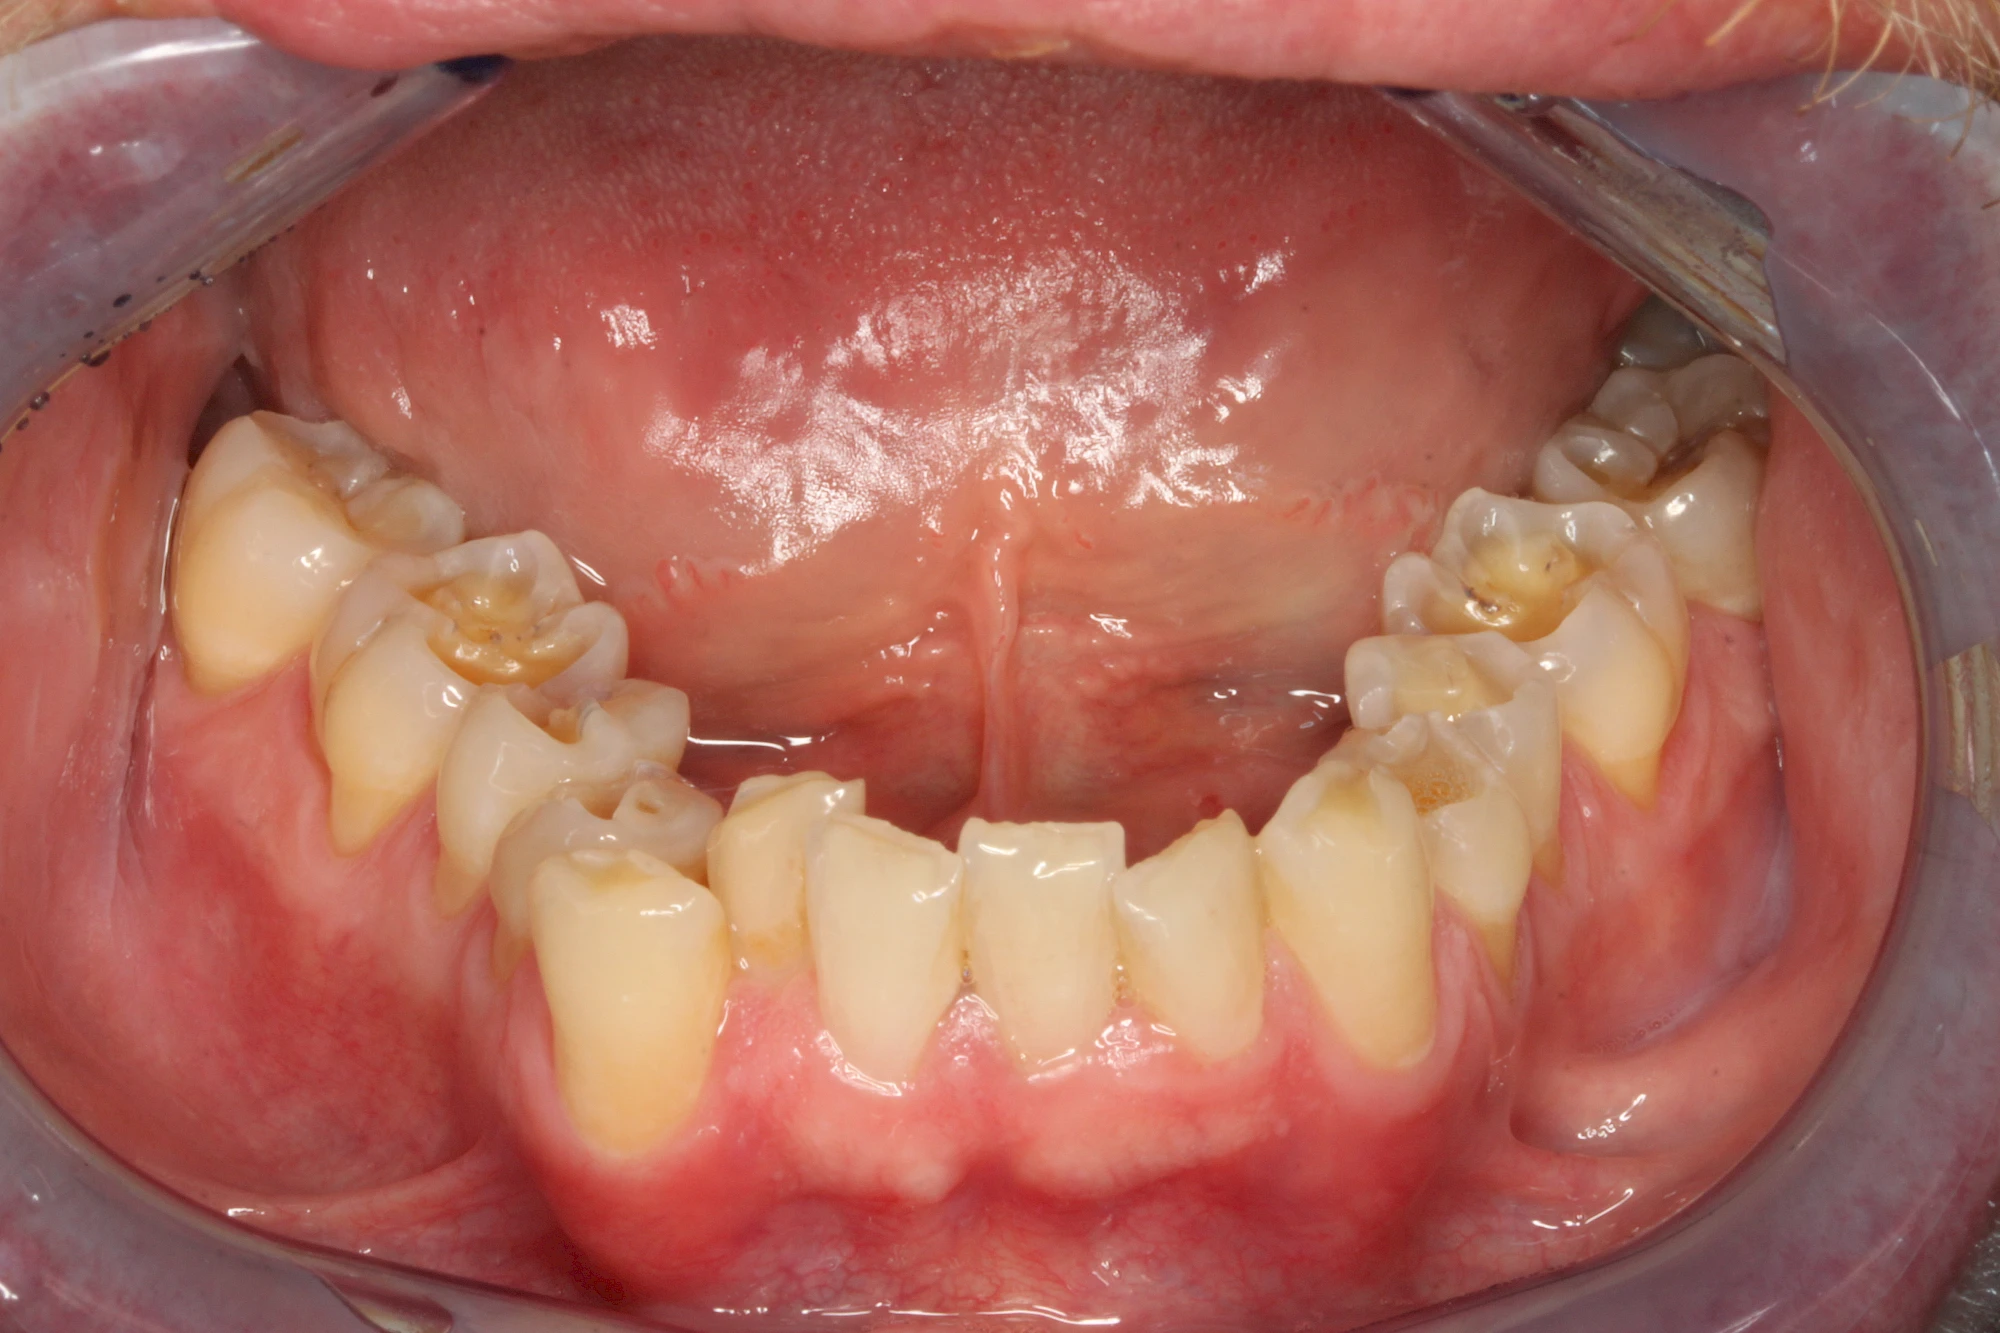

Über die Zeit können verschiedene Prozesse die Zahnhartsubstanzen aufzehren:

- Abnutzung durch Kauen (Abrasion) oder duch durch übermäßiges Knirschen bzw. Pressen (Attrition)

- Säurebedingte Auswaschung (Erosion)

- Knirschen bzw. Pressen und ungünstige Putztechnik (Druck): keilförmige Defekte

Die Zähne können dabei auf Reize (warm, kalt, süß, sauer) oder auch beim Zähneputzen empfindlich oder schmerzhaft sein. In allen diesen Fällen ist es sinnvoll, den Zahnarzt zu kontaktieren und das weitere Vorgehen abzustimmen.